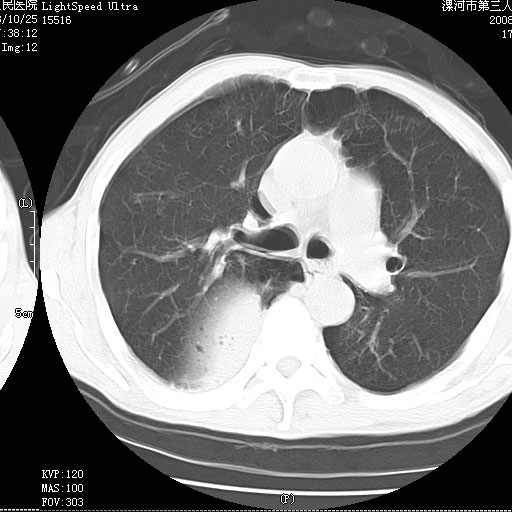

3、细支气管肺泡癌可以排除,病变以斜裂为界,呈大片状高密度影,内可见多发小气泡,表明有产气杆菌感染所致,内无明显的支气管“枯树枝征”表现,再结合其临床改变(细支气管肺泡癌临表表现重、影像表现轻)所以不符合细支气管肺泡癌(炎症型)的改变。

病变按肺叶分布,病变内可见多个小空腔影,未见充气支气管影,中间段支气管管腔肺窗示密度欠均匀,下肺支气管分叉处基底段支气管隐约可见,未见明显狭窄,中叶支气管通畅,

考虑:阻塞性肺炎伴小脓肿形成可能性大。(痰栓可能性大)

右下肺实变,内有弥漫分面小气泡而无支气管征,叶间裂前移,呈臌大之形,而无收缩之状,兼纵隔稍左行移,故。不支持不张,倒支持大叶肺叶,如楼上所说,小气泡不象残留之肺,不可以考虑产气菌感染吗。

阻塞性肺炎,肺脓肿形成。依据,右下支气管不通,大片实变形内可见小气泡。不支持肺不张。